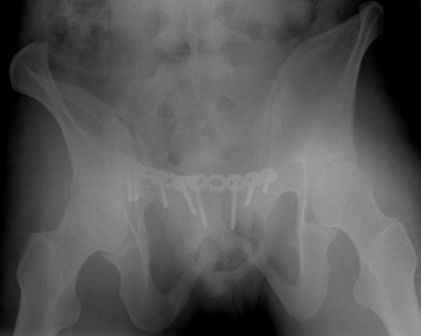

Спасибо за полезные советы! По inlet и outlet обнаружили перелом крестцас той-же стороны. Сегодня прооперировали реконструктивной пластиной с перекрытием симфиза, крестец, увы, фиксировать было нечем - оставили так (тем более, что грубой дислокации там нет). Рентгенограммы выложу позже.

Здравствуйте, Евгений! Надо было делать комбинированный остеосинтез, как предлагал Алексей: пластину на лоно+стержневой аппарат.

Серия до- и послеоперационных снимков этой пациентки. Хотя бы post factum обсудить. Не знаю, что можно сделать с задними отделами стержневым аппаратом, но три крепких парня открытым путем с помощью "волшебных" слов еле-еле смогли отрепонировать - сзади все было очень ригидно!

Здравствуйте, Евгений! У меня видна только дооперационная проекция inlet.

я бы остановился на передней раме, операция - 30 мин, в таком варианте вроде бы репозиция - ничего, но когда давать нагрузку, ведь в лонном сочленении тоже есть подвижность? а если не давать - зачем операция?